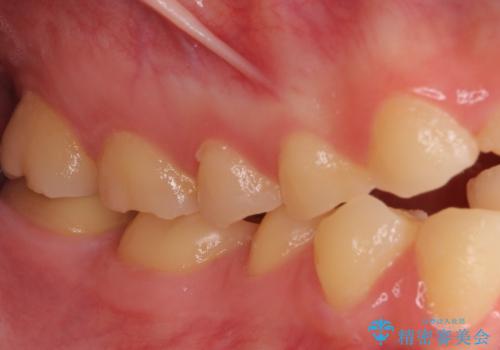

酸によりエナメル質の大半が溶けており、下顎前歯以外は酷いむし歯のような状態でした。

当初はほとんどの歯をむし歯治療のようにオールセラミッククラウンにて補綴治療を行う予定でしたが、仮歯に置き換えた時点で、口元の突出感や下顎前歯の叢生が気になるとのことで、上下左右の第一小臼歯4本を抜歯したワイヤー装置での抜歯矯正を行うこととしました。